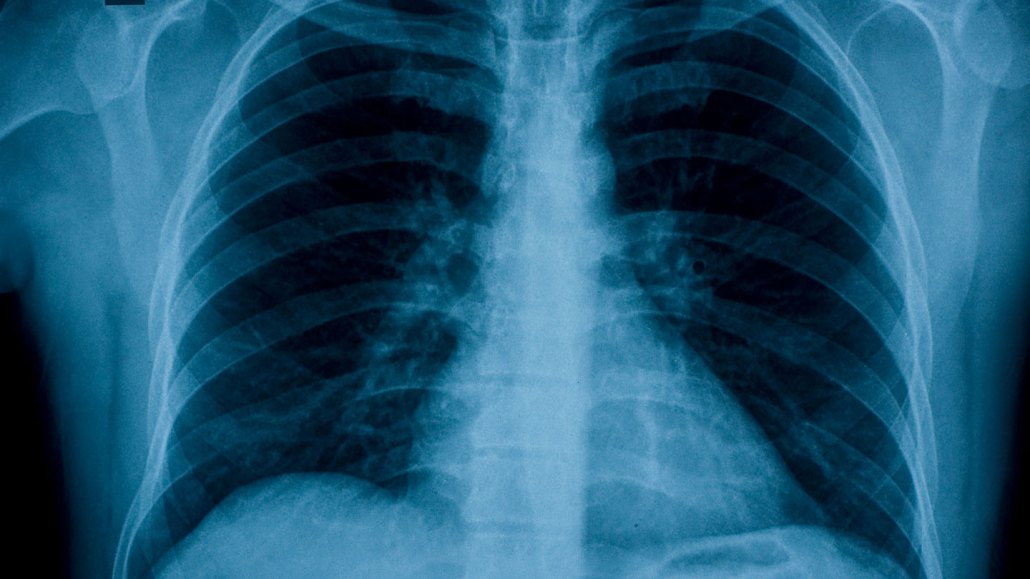

An X-ray image of the chest, shown in shades of white, blue and black. AI models can scan these medical images and reveal health information.

AI computer models can scan medical images like this chest X-ray and glean details about a person’s cardiovascular and metabolic health.